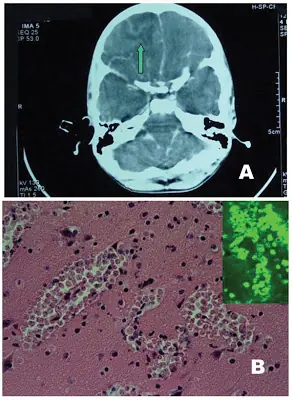

Esta rara forma de meningitis por parásitos, la meningoencefalitis amebiana primaria, está causada por la ameba 'Naegleria fowleri', que normalmente se alimenta de bacterias y suele vivir en la capa sedimentaria de los lagos cálidos y estanques.

"Cuando la gente se baña en aguas dulces templadas durante el verano, la ameba puede penetrar en el cerebro a través de las fosas nasales. Esto causa dolor de cabeza, tortícolis y vómitos, que progresa hacia síntomas más graves. Entre la exposición y el inicio, la infección generalmente deriva en un estado de coma y la muerte al cabo de unos cinco días", dijo el experto.